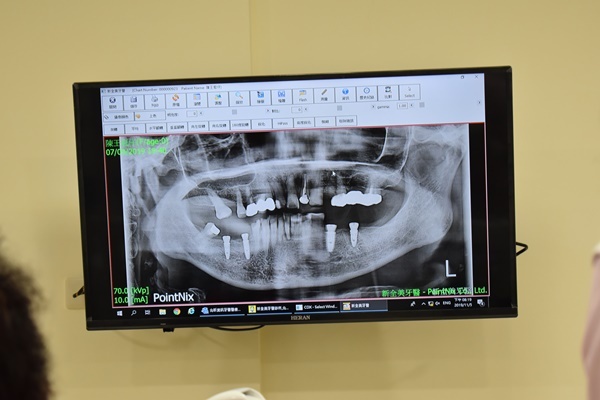

Q:倘若有多顆缺牙問題該怎麼治療比較好呢?

A:多顆缺牙治療方式有很多種,植牙/牙橋/活動假牙/植牙搭配牙橋/植牙搭配活動假牙/全口活動假牙,專業的牙科醫師會針對病患能負擔的治療方式進行建議,遇到多顆缺牙問題務必跟牙醫師多討論才能有效解決缺牙困擾